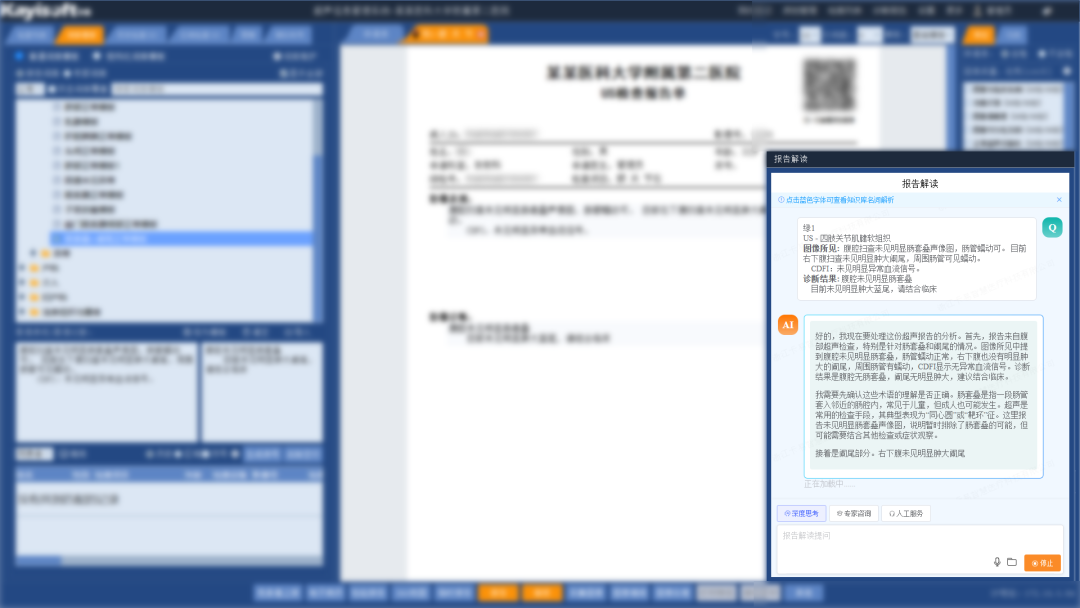

报告解读:通过DeepSeek提供贴心的影像报告解读服务,旨在帮助患者轻松理解检查结果和自身病情,通过将复杂专业的医学术语转化为通俗易懂的白话,有效缓解患者的焦虑情绪。平台支持拍照、自助上传报告PDF或报告图片以及语音解析等多种便捷方式,极大地提升了用户体验,让获取医疗信息变得更加方便快捷。

名词解析:点击蓝色字体可查看知识库名词解析,有助于患者更好地理解自己的病情、治疗方案以及预防措施,从而做出明智的健康决策。根据患者的病情和检查结果,推送相关的健康教育内容,例如疾病知识、预防措施、治疗方案等。

影像咨询:当患者对查看的影像或报告内容存在疑问时,可在报告界面直接发起影像咨询,借助DeepSeek获取关于检查流程、报告解读、病情咨询等方面的便捷、专业、优质且经济的建议与服务。若仍有不解,患者还可一键点击专家咨询,迅速发起线上问诊,由平台专家提供权威解答,这一流程不仅极大地优化了患者的就医体验,也显著提升了医疗服务的效率与质量。